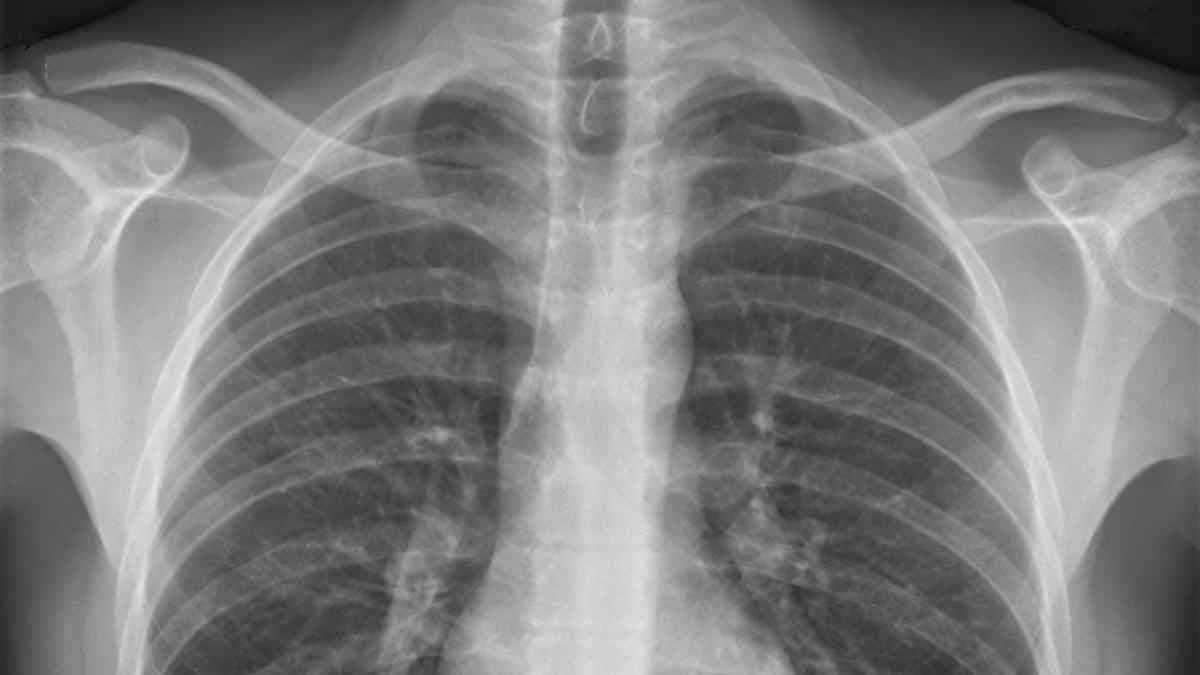

La exposición continuada a este agente puede causar silicosis y cáncer de pulmón, ambas patologías reconocidas como 'Enfermedades Profesionales' por el sistema sanitario español. UGT FICA espera que la Dirección General de Ordenación de la Seguridad Social estime la solicitud e inicie el análisis de viabilidad.